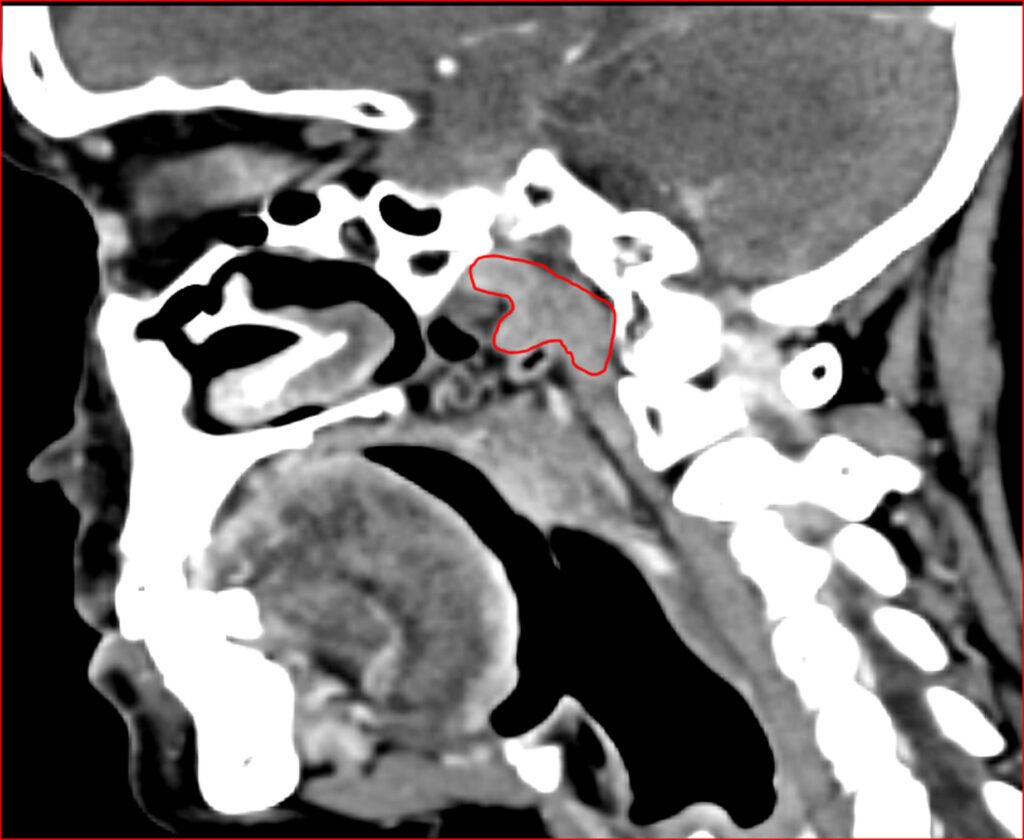

The researchers were using a specialized imaging method called PSMA PET/CT scanning. PSMA stands for Prostate-Specific Membrane Antigen — a molecule highly expressed in prostate cancer cells. These scans are commonly used in oncology to detect prostate cancer spread.

According to the National Cancer Institute, PET scans work by using radioactive tracers to highlight metabolically active tissue. In this case, PSMA tracers also bind to salivary gland tissue.

While scanning over 100 prostate cancer patients, researchers noticed consistent tracer uptake in the same region of the nasopharynx. That raised eyebrows.

To confirm their observations, the team examined cadavers and identified glandular tissue in that location. The findings were published in the peer-reviewed journal Radiotherapy and Oncology.

Radiation oncologists already try to spare major salivary glands. If these newly described glands are confirmed as functionally important, treatment planning software and contouring guidelines may eventually include them.